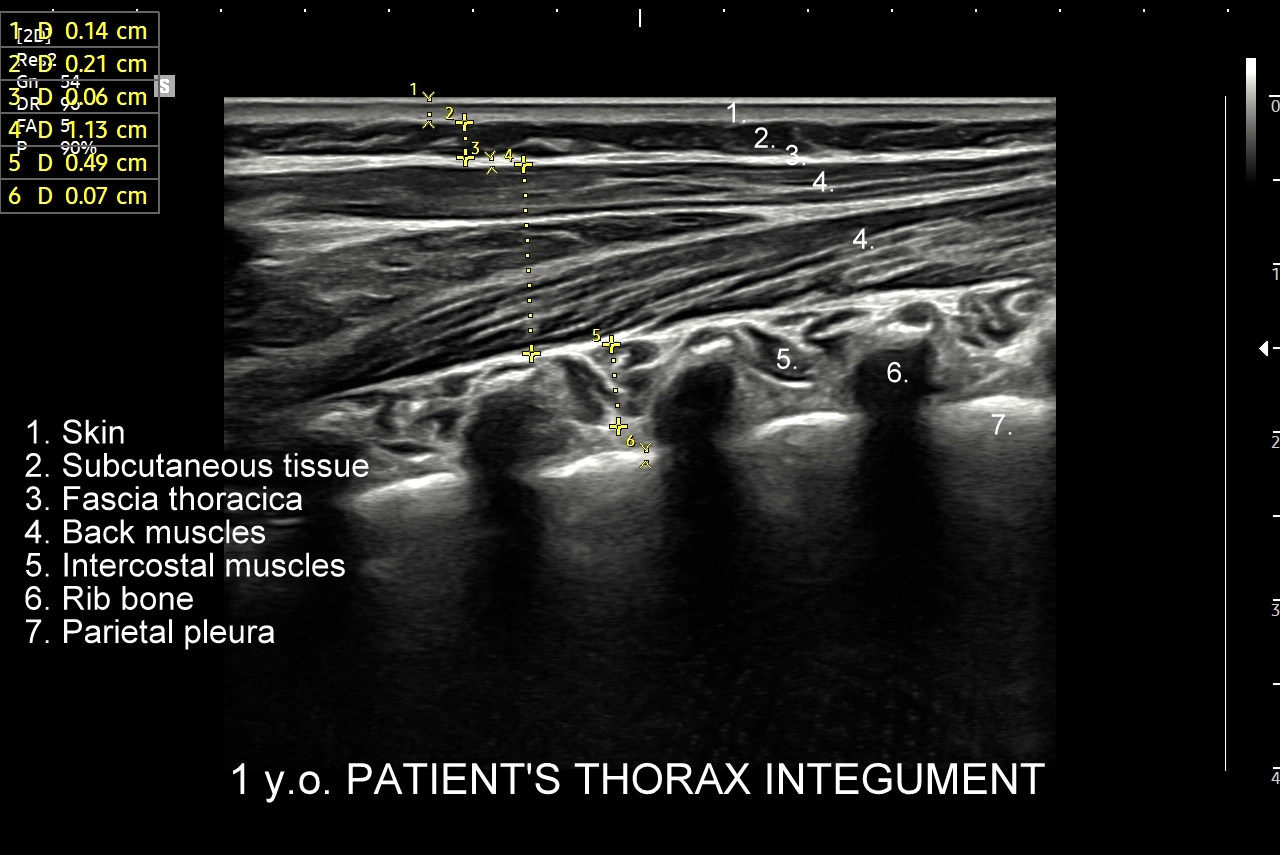

Ultrasonografia płuc oparta jest o fizykę fal akustycznych. Wychwytuje zarówno schorzenia lokalizujące się w zewnętrznych partiach płuc oraz w jamach opłucnowych w postaci realnego obrazu, ale także wykazuje istotne diagnostycznie informacje z głębszych partii narządu na podstawie specyficznych artefaktów generowanych przez patologie wewnątrz płuca.

Pokrewne badanie USG ścian klatki piersiowej przydatne jest z kolei w diagnostyce stanów urazowych i przeciążeniowych w obrębie układu szkieletowego klatki piersiowej, takich jak złamanie żeber, zespół Tietza, czy naderwanie mięśni. USG klatki piersiowej wykorzystywane jest również przy ocenie zmian guzowatych w powłokach klatki, których przykładami są tłuszczaki, kaszaki, krwiaki, mięsaki i przerzuty nowotworowe.